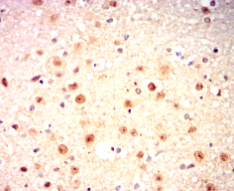

IHC    1/200 - 1/1000